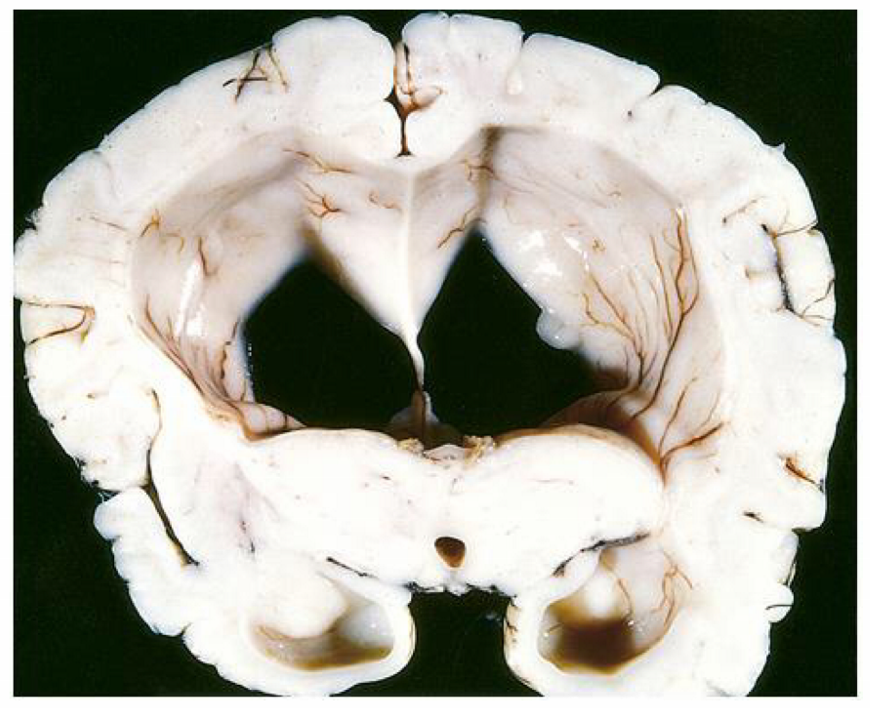

in the communicating form of the condition seen in the image, there is dilation of ___

in the communicating form of the condition seen in the image, there is dilation of ALL ventricles

the communicating form of the condition seen in the image can due to scarring/fibrosis of ____ or ____

the communicating form of the condition seen in the image can due to scarring or fibrosis of the arachnoid villi d/t tumors or infxns (TB, meningitis) or subarachnoid hemorrhage

the communicating form of the condition seen in the image is caused by reduced ____, such as in ____

the communicating form of the condition seen in the image is caused by reduced CSF resorption, such as in arachnoid fibrosis

the normal pressure form of the condition seen in the image is characterized by the triad of:

wet = urinary incontinence

wobbly = ataxia

the ex vacuo form of the condition seen in the image causes dilation of ____ due to ____ and causes a compensatory ____

the ex vacuo form of the condition seen in the image causes dilation of all ventricles due to cerebral atrophy and causes a compensatory increase in CSF

the non-communicating form of the condition seen in the image occurs between ____ & ____ or between ____ & _____

the non-communicating form of the condition seen in the image occurs between lateral & 3rd ventricle or between 3rd & 4th ventricle

the presentation of condition seen in the image in children is increased ____ because ____

the presentation of condition seen in the image in children is increased head circumference because skull bones (fontanelles & sutures) have not fused yet

the presentation of condition seen in the image in adults is increased ____

the presentation of condition seen in the image in adults is increased ICP

a complication of the condition seen in the image is ___ which is a triad of symptoms indicating an impending ____

a complication of the condition seen in the image is Cushing’s reflex which is a triad of symptoms indicating an impending herniation

• elevated systolic pressure (wide pulse pressure)

• bradycardia

• irregular respirations